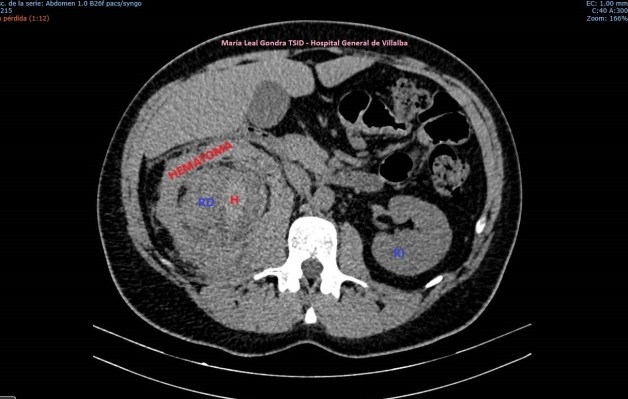

He comentado antes  que en ocasiones se le puede realizar a una paciente una galactografía, sobre todo cuando la secreción es por un solo conducto, y además sanguinolenta, pero es decisión de las doctoras, como ya he comentado. Esta prueba es la Galactografía, antes era muy habitual su realización, cada día más en desuso, te dejo la imagen 9 para que aprecies la belleza de esta técnica donde se usa un contraste que se inyecta previa canalización del agujero correspondiente al conducto que tiene la secreción, usando el mamógrafo para esta técnica.

9

10

Imagen 9 e imagen 10 son dos técnicas diferentes, que guardan una correlación muy evidente en la representación de los conductos galactóforos que van a buscar el pezón.